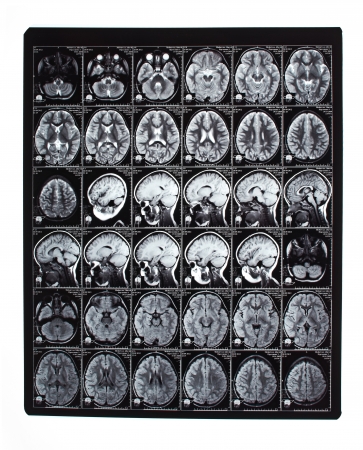

El uso de herramientas de diagnóstico mediante imagen ha ido creciendo a lo largo del tiempo, y además de ser profusamente utilizado, supone un elemento muy importante del coste: donde antes un médico tenía que procesar manualmente unas pocas imágenes, ahora es perfectamente habitual que en una sola prueba se obtengan cientos o incluso miles de imágenes en finas capas, en procesos que pueden llegar a ser profundamente aburridos y que incrementan la probabilidad de error debido al cansancio o la pérdida de atención.

Una imagen de diagnóstico médico es un fichero digitalizable o, cada vez más, directamente digital. Convertir esas secuencias de píxeles en elementos capaces de ser procesados algorítmicamente es algo que cae perfectamente dentro de las posibilidades del machine learning, en un ámbito, el de la imagen, en el que ya se han obtenido numerosos progresos. Que lleguemos a un momento en el que el análisis de una imagen se lleve a cabo directamente tras su obtención, o incluso durante la misma – para permitir un muestreo más exhaustivo de determinadas áreas – o, incluso, a un momento en el que los médicos directamente pierdan la capacidad de utilizar ese método diagnóstico por falta de práctica es algo que, a día de hoy, cabe perfectamente dentro de los escenarios posibles. En este momento, un algoritmo es capaz de procesar e interpretar una resonancia magnética de corazón, por ejemplo, en unos quince segundos, un examen que puede necesitar unos 45 minutos cuando lo lleva a cabo un cardiólogo o radiólogo.